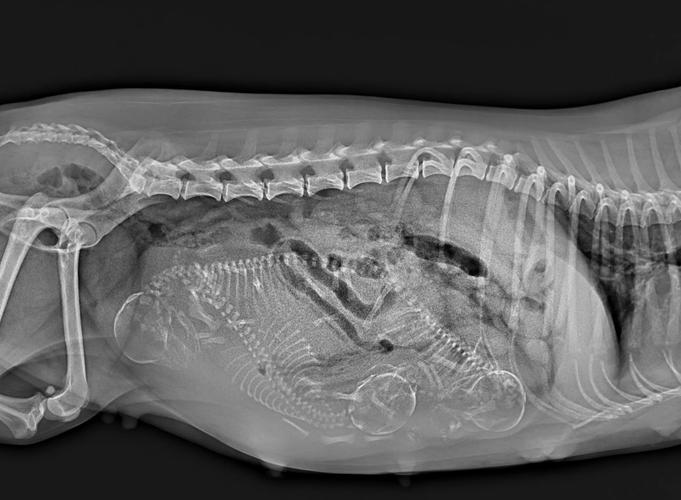

〖Two〗、狗狗在怀孕期间是否可以洗澡需要根据具体情况谨慎决定,以下是关键注意事项: 怀孕阶段 早期(前3周):胚胎着床不稳定,洗澡的应激反应或温度变化可能增加风险,建议避免。中后期(4周后):若狗狗健康且适应洗澡,可温和清洁,但需缩短时间、避免腹部压力。

〖One〗、狗狗在怀孕的时候大部分情况下能洗澡,但有以下限制和注意事项:时间限制:狗狗在刚刚怀孕的一个月内和预产期前20天是不可以洗澡的。这两个时间段内,狗狗的身体较为敏感,洗澡可能会对其造成不良影响。保暖措施:在给怀孕的狗狗洗澡时,必须做好保暖措施,确保狗狗不会着凉感冒。

〖Four〗、狗狗怀孕能洗澡,不过在两个月的妊娠周期中,中间的一个月时间相对比较安全,此时可以按照15天左右洗一次澡,如果狗狗妊娠反应较大、或是平时对洗澡就比较抵触,也不必勉强它,可以适当拉长洗澡间隔,妊娠期的最后一次洗澡应该选取在预产期的前10『1』5天,此后,要一直到小狗断奶才能洗澡。

〖Two〗、怀孕初期:不建议洗澡。此时泰迪狗的身体较为敏感,洗澡容易造成感冒,对胎儿和母体都不利。怀孕中期:可以洗澡,但动作需要轻、快。避免用力揉搓狗狗的腹部,以防动了胎气。洗澡后及时用吹风机将毛发吹干,防止感冒。怀孕晚期:不宜洗澡。

〖Three〗、泰迪狗怀孕期间需要注意以下事项:洗澡问题:前两个星期和后两个星期避免洗澡。这是为了防止狗狗因洗澡而感冒或受到其他不必要的刺激,影响其身体健康和胎儿的安全。适量运动:每天保持半小时以上的适宜运动。适当的运动有助于泰迪狗保持身体健康,促进胎儿的正常发育。避免剧烈运动。